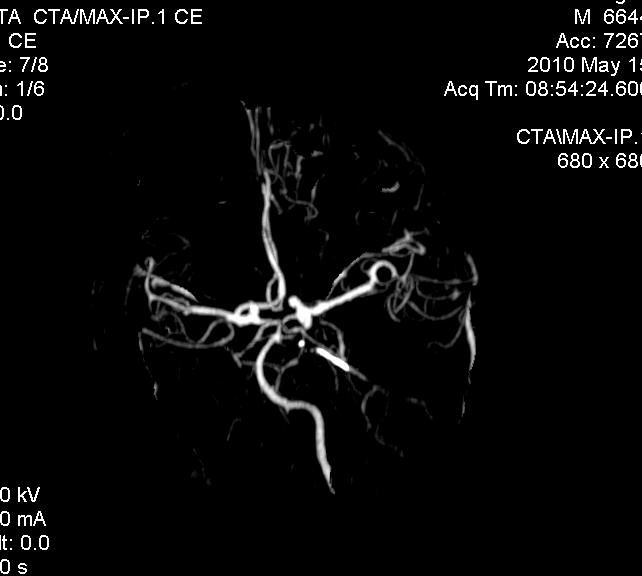

男.60岁,渐进性意识不清,ct检查双侧额颞顶部硬膜下血肿,开颅术后行脑血管cta,大脑中动脉起始部见一瘤状血管扩张。请各位老师留下宝贵意见

太常见了,报动脉瘤就可以

符合动脉瘤表现。

符合动脉瘤表现。

动脉瘤。

颅内动脉瘤。

后重建做得不是很好看,要将维蒂斯环充分显示,最好在增加一个mip。这样不好定位。

小动脉瘤

典型

符合动脉瘤的表现

动脉瘤

符合动脉瘤表现。

小动脉瘤

典型